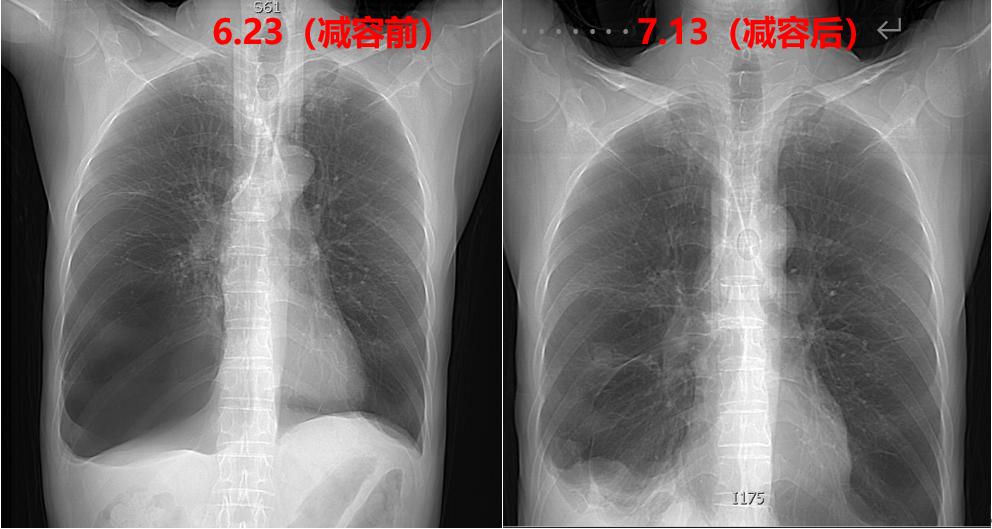

图1一名慢性阻塞性肺疾病(COPD)并巨大肺大疱伴有II型呼吸衰竭的患者,经吸入性糖皮质激素(ICS)+吸入型长效β2受体激动剂(LABA)+长效抗胆碱能拮抗剂(LAMA)、家庭氧疗等治疗,胸闷仍然频繁发作,患者焦虑、烦躁,每日自行使用超量气道扩张剂,对于这类患者,内科医生该如何处理?

2021.06.23 胸部CT平扫:1.肺气肿,肺大疱;右肺中叶巨大肺大疱伴部分肺组织膨胀不全;2.两肺上叶陈旧灶,两肺少许纤维灶;3.主动脉钙化。

2021.07.13 胸部CT平扫:1.右肺大疱减容术后,右侧胸腔积液;2.左侧肺大疱;3.两肺上叶陈旧灶,两肺少许纤维灶;4.主动脉钙化。

图2-4入院后完善相关检查,于2021.06.25行全麻下胸腔镜下肺大疱减容术(右侧),术后予以镇痛、抗感染、止咳平喘、经鼻高流量氧疗(HFNC)等治疗。

术后胸腔闭式引流、肺功能康复等处理,术后第3天复查胸片,提示右侧减容术后肺复张良好,拔除胸腔闭式引流管,肺减容术后患者活动耐量明显改善,不吸氧脉氧达95%,可以在病房自由活动,自诉“以前吸气吸不到底,现在终于可以了”,患者之后经康复治疗后出院。